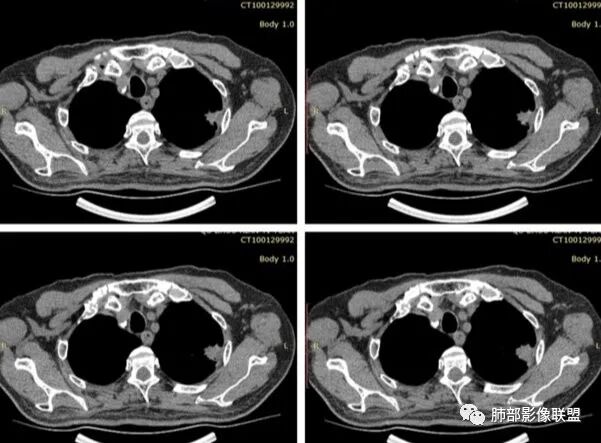

1、患者老年男性,无明显临床症状。

2、病灶位于左肺上叶尖后段,符合肺结核好发部位。

3、病灶密度不均,可见钙化点,未显示空洞或液化。边缘收缩,U型凹陷、桃尖征、细长毛刺以及较长棘状突起。宽基底与胸膜相连,邻近胸膜广泛性增厚(未见栽赃侵入)。可见卫星病灶,周围的磨玻璃影比较松散,炎性病变征象多,符合结核的CT表现。

4、部分区域膨隆,未见支气管截断,肺门纵隔未见肿大淋巴结等,恶性征象少。

5、结合其无临床症状、病灶形态、病灶位置及发病率,结核居多,最后诊断在大家意料之中。